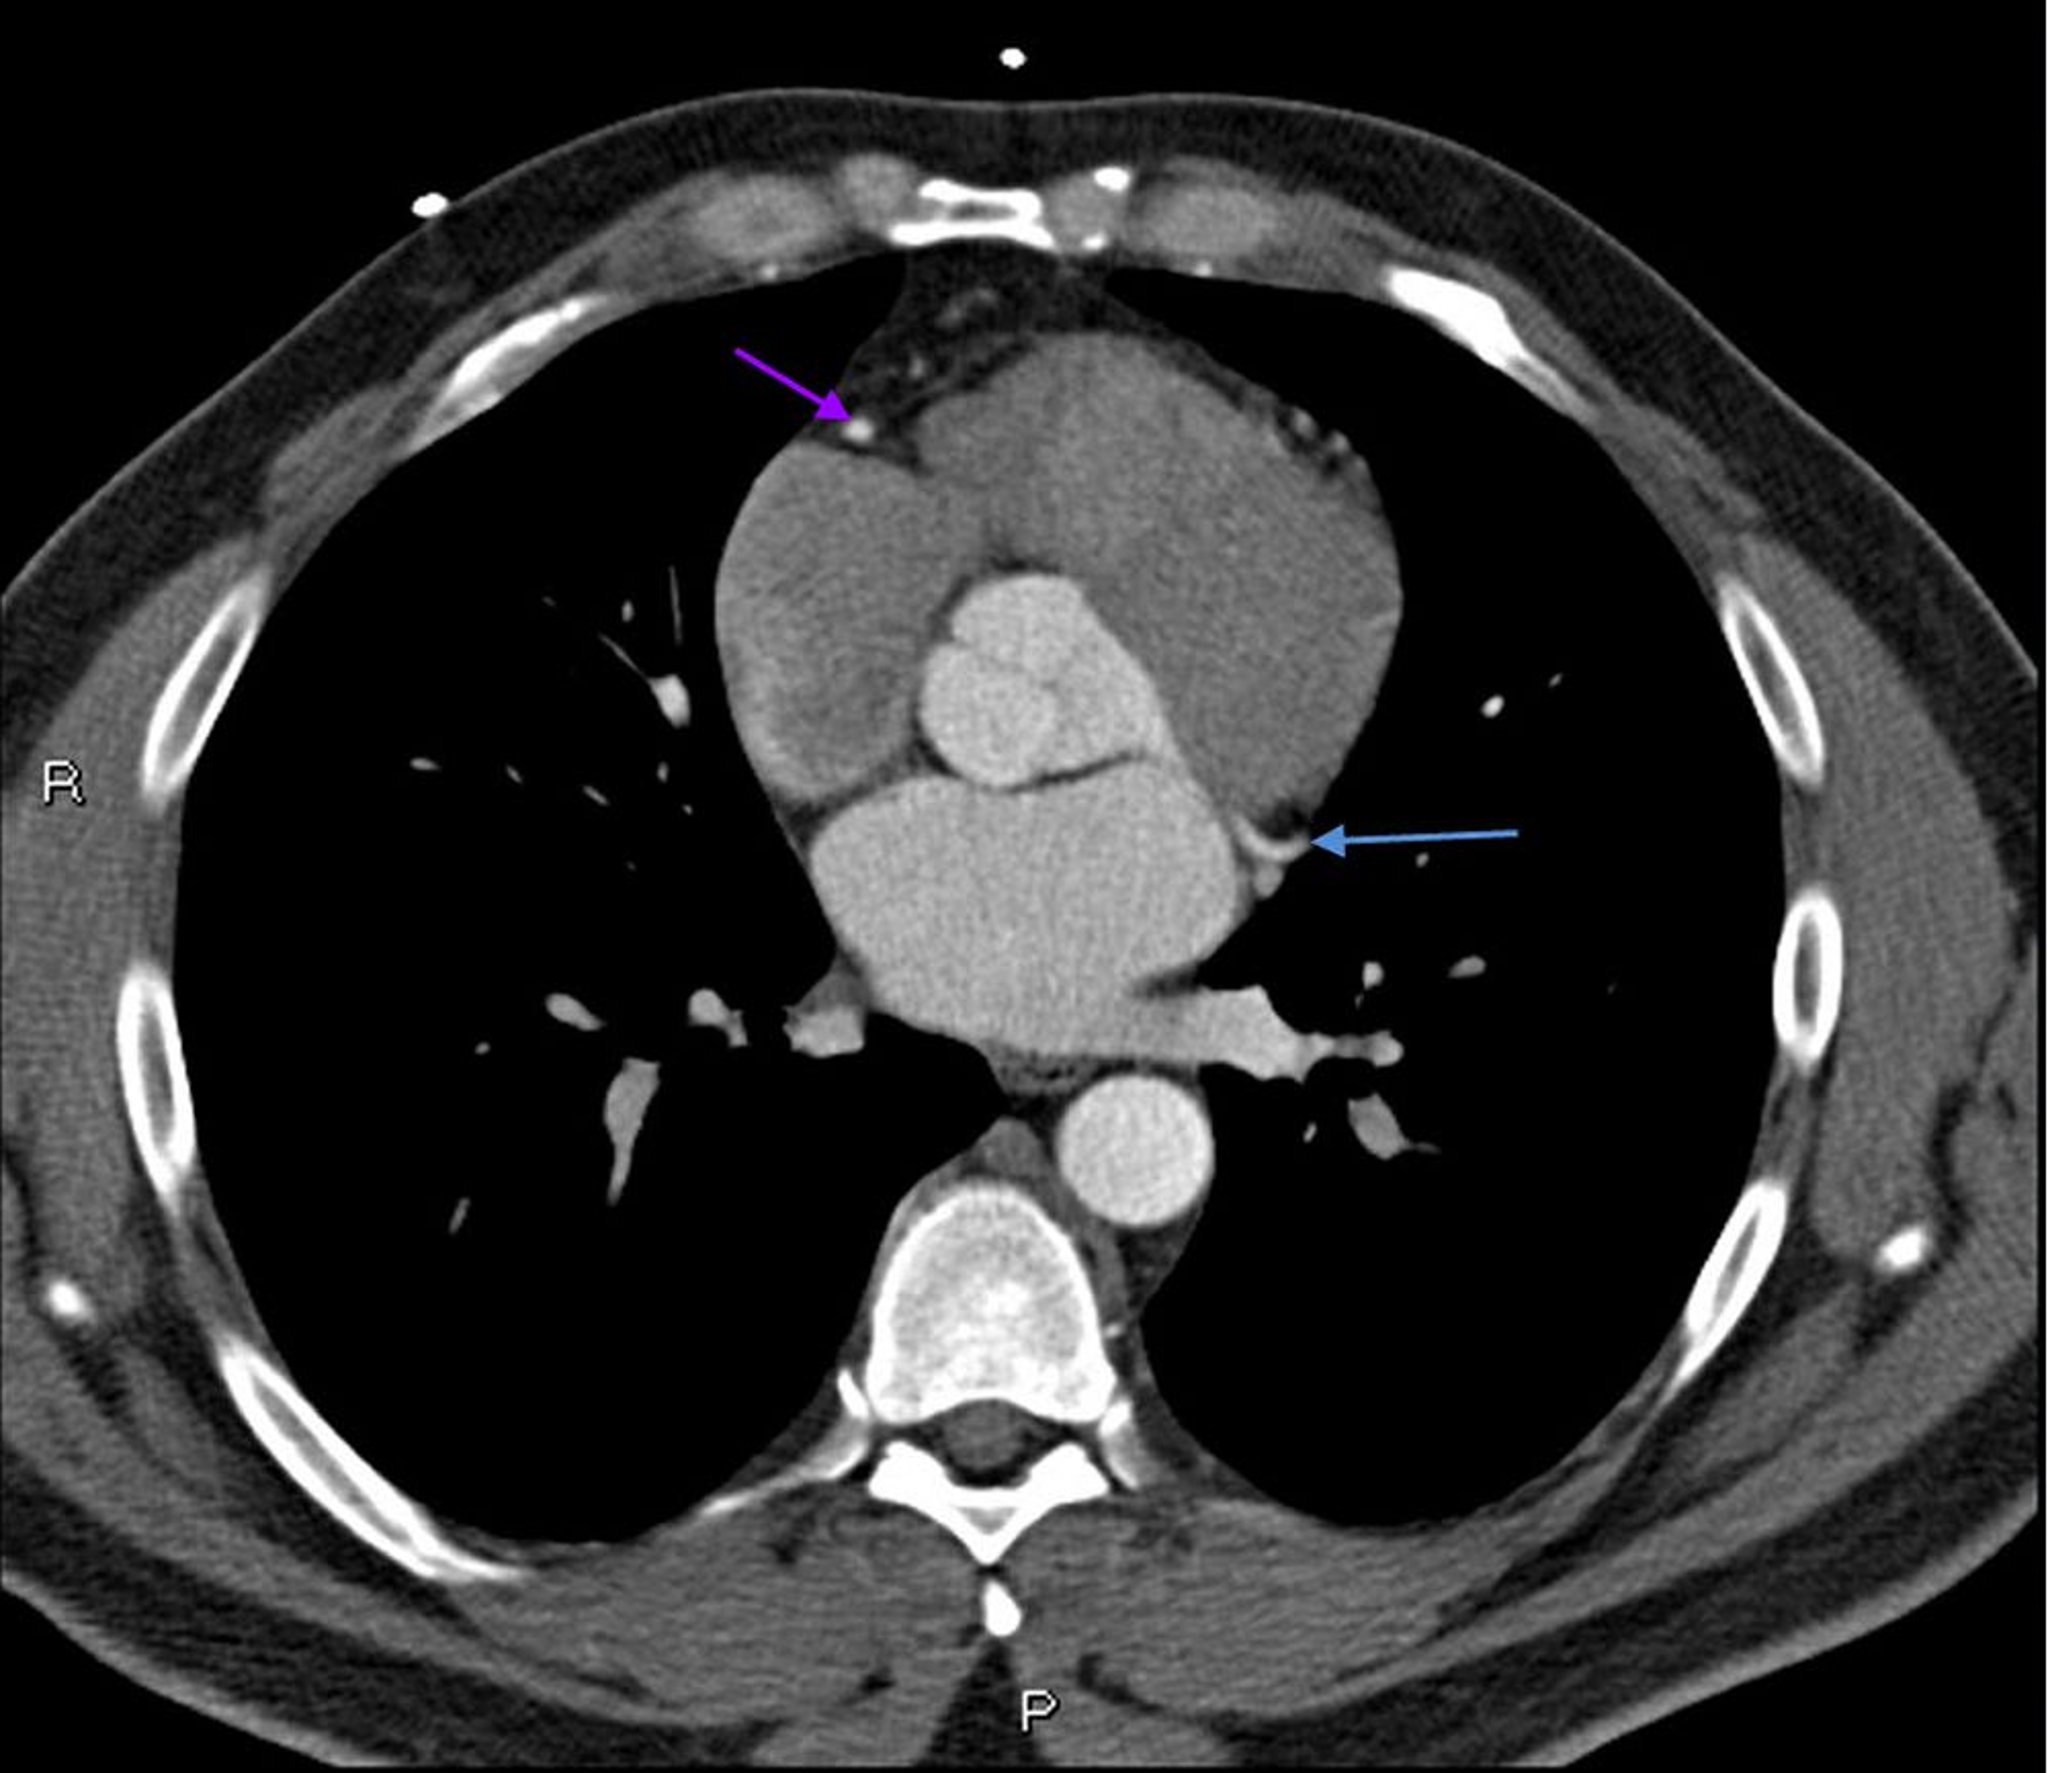

КТ с контрастированием, показывающая коронарные артерии в норме – слайд 6

КТ с контрастированием, показывающая коронарные артерии в норме Левая ветвь коронарной артерии обозначена красной стрелкой. Левая передняя нисходящая и левая огибающая артерии обозначены зеленой и синей стрелками соответственно, а правая коронарная артерия – филетовой стрелкой.